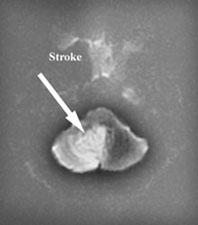

MRI or angiography are adjunct diagnostic methods. Magnetic resonance imaging can be used to create pictures of the brain and can also be used to create pictures of a blood vessel so called MR angiogram (MRA).

By these techniques the doctors can pinpoint the area of stroke in the brain as well as the area of blockage of the vessels.

DWI